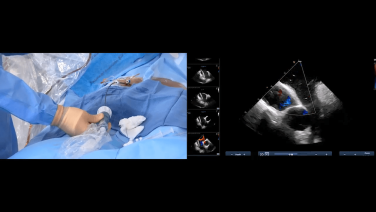

Utilizing Intracardiac Echo During Transseptal Puncture with Brett Gidney, MD